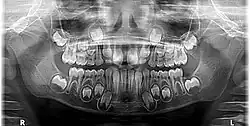

O dente decíduo é o dente que surge durante a ontogenia de humanos e outros mamíferos.[1] O desenvolvimento dentário começa durante o período embrionário e os dentes tornam-se visíveis (erupção dentária) na boca durante a infância. Esses dentes são popularmente conhecidos como dentes de leite, cuja denominação surgiu devido a sua coloração ser mais branca, opaca e leitosa. Quando comparados aos permanentes se apresentam em menor tamanho e possuem as raízes mais curtas, além de não possuir os pré-molares e sisos.[2] A dentição decídua completa é composta por 20 dentes.[3]

O dente decíduo é menos mineralizado do que o dente permanente, sendo bem mais branco que os dente permanente. Se uma criança apresenta dentição mista, com dentes decíduos e permanentes, é fácil identificar quais são os dentes permanentes, já que eles tendem a ser um pouco maiores e com uma coloração mais amarelada.[11] Uma vez que os dentes decíduos estão fadados a cair, possuem raízes com formato diferente dos dentes permanentes. As raízes da dentição decídua são mais finas quando comparadas as raízes dos dentes permanentes. Outra grande diferença entre os dentes primários e os dentes decíduos é o número deles. Normalmente, as pessoas têm 20 dentes de leite e 32 permanentes, incluindo os quatro dentes do siso. A falta (agenesia dentária[12]) ou acréscimo (dente supranumerário) de elementos dentários pode ocorrer e é uma alteração comum. Parte do que determina a diferença em termos numéricos é o fato de que a boca de uma criança é muito menor que a de um adulto, as crianças não têm espaço para 8 a 12 molares. No entanto, à medida que as crianças crescem, a mandíbula também cresce dá espaço aos dentes adicionais.[13]

Na dentição decídua há 20 dentes no total: 8 incisivos, 4 caninos e 8 molares decíduos.